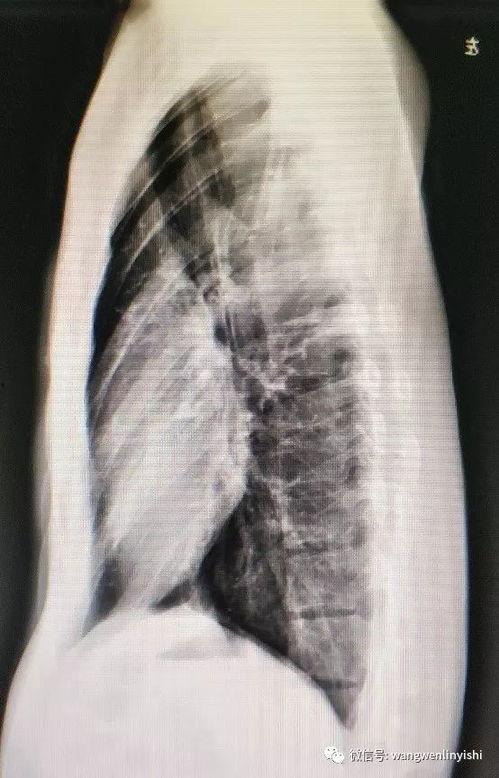

二、身体变化:直观展示病情

手术前照片最直观的作用就是展示患者的身体变化。通过这些照片,医生可以更准确地判断病情,制定手术方案。比如,一位患有甲状腺肿瘤的患者,手术前的照片清晰地显示了肿瘤的大小和位置,为医生提供了重要的参考依据。